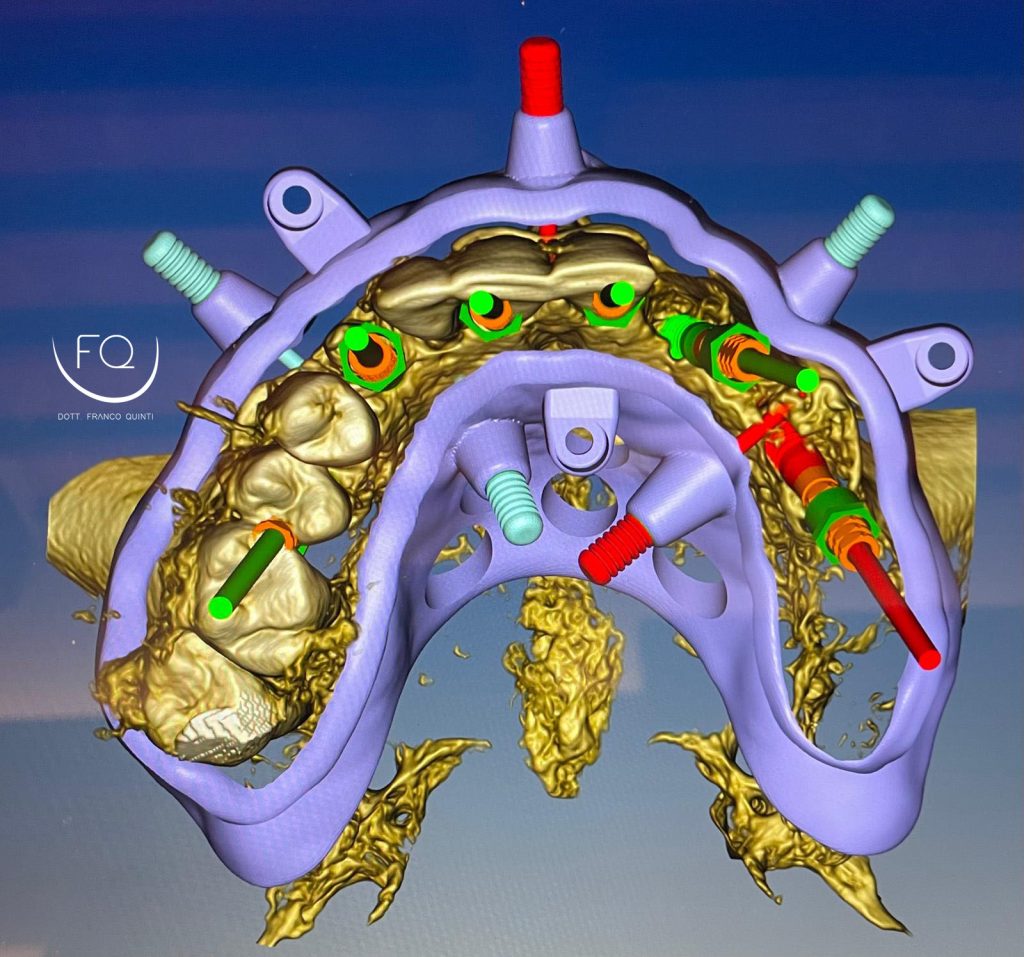

Questa settimana vi presento un caso di chirurgia computer guidata dell’arcata superiore realizzato con dime scomponibili con esecuzione contestuale di un carico immediato.

Nelle prossime settimane vi mostrerò dei brevi video di questo caso relativi alla scomposizione e alla progettazione delle dime chirurgiche.